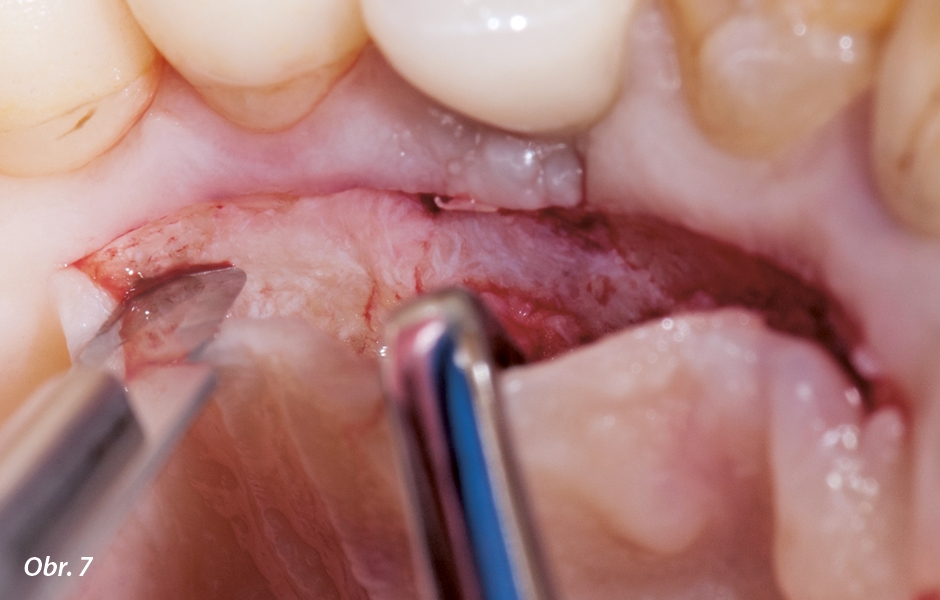

Podložní štěp CTG se oddělí od okolní pojivové tkáně několika řezy směrem ke kosti z meziální, distální a středové části štěpu. Štěp pak lze odebrat jeho oddálením od povrchu kosti pomocí periosteálního elevátoru (obr. 7, 8, 9). Pomocí této techniky je možné získat štěp o tloušťce 1,5 až 2,9 mm34 (obr. 10). Po odběru se štěp CTG umístí na gázu nasáklou fyziologickým roztokem a ponechá se zvlhčený až do okamžiku transplantace na místo určení. Před suturou je možné do mezery po štěpu CTG podmíněně umístit kolagenní materiál (např. Avitene, Davol)36, 37 a zachovat tak po zhojení vnější obrys patrové sliznice. Použití techniky pouze jednoho řezu bez odebrání epitelu usnadňuje opětovnou adaptaci tkáně v místě řezu. Úhel čepele vůči kosti 90 stupňů při prvním řezu vytváří tupé spoje. Namísto přerušovaných stehů se používají horizontální matracové stehy, které zajistí okraje laloku a současně celou podložní dárcovskou oblast. Tyto stehy mohou být paralelní a/nebo křížové (obr. 11, 12).